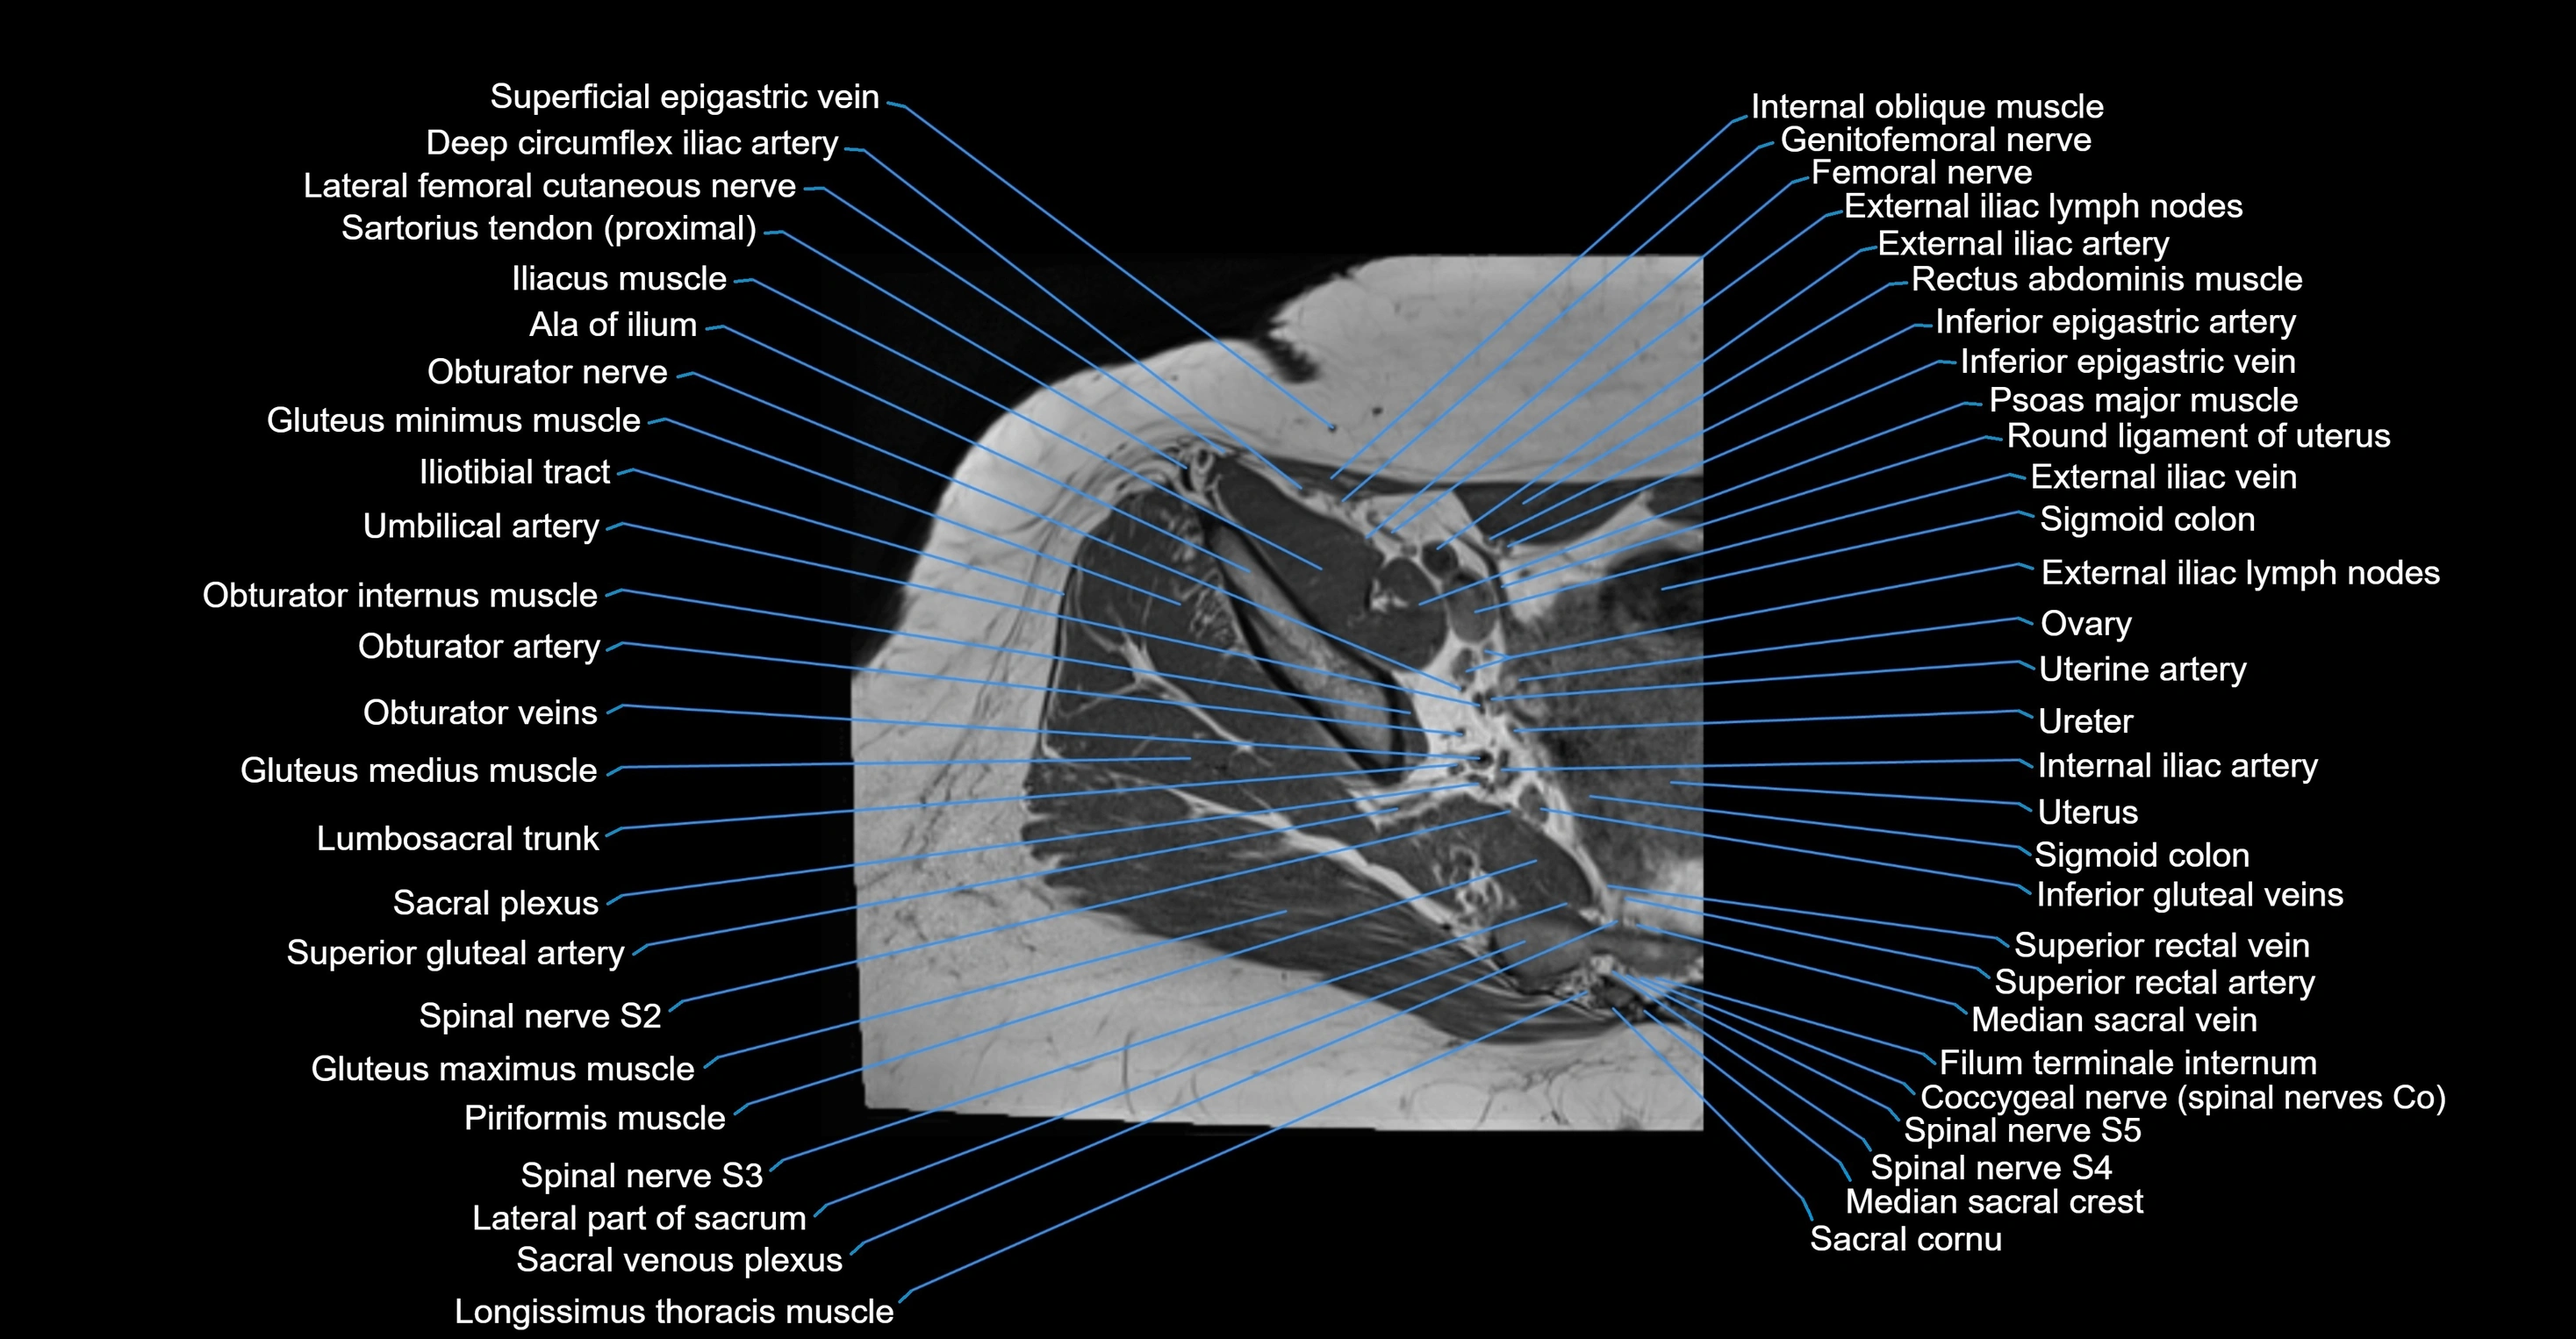

- Deep circumflex iliac artery

- External iliac lymph nodes

- External iliac vein

- Filum terminale internum

- Genitofemoral nerve

- Gluteal lymph nodes

- Gluteus maximus muscle

- Gluteus medius muscle

- Gluteus minimus muscle

- Iliotibial tract

- Inferior epigastric artery

- Inferior epigastric veins

- Internal iliac artery

- Internal iliac lymph nodes

- Lateral part of sacrum

- Lumbosacral trunk

- Median sacral crest

- Median sacral vein

- Obturator internus muscle

- Ovaries

- Psoas major muscle

- Round ligament of uterus

- Sacral plexus

- Sigmoid colon

- Spinal nerve S2

- Spinal nerve S3

- Spinal nerve S4

- Spinal nerve S5

- Superior gluteal artery

- Superior rectal vein

- Umbilical artery

- Uterine artery

- Uterus